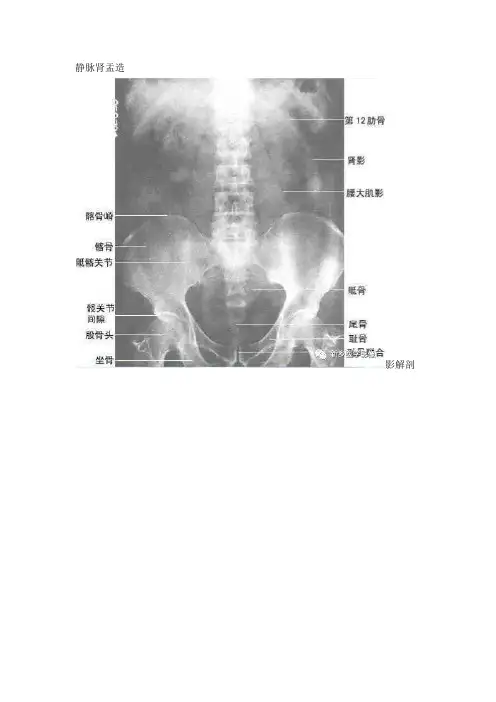

静脉肾盂造影解剖静脉肾盂造影适应症1.适应证①尿路结石、结核、囊肿、肿瘤、慢性炎症和先天性畸形,②原因不明的血尿和脓尿; ③尿路损伤; ④腹膜后肿瘤的鉴别诊断;⑤肾性高血压的筛选检査;⑥解腹膜后包块与泌尿系的关系.2. 禁忌证①碘过敏及甲状腺功能亢进者; ②严重的肾功能不良者;③急性尿路感染;④严重的心血管疾患及肝功能不良;⑤妊娠或疑有早期妊娠者。

静脉肾盂造影解剖静脉肾盂造影适应症1、适应证①尿路结石、结核、囊肿、肿瘤、慢性炎症与先天性畸形,②原因不明得血尿与脓尿; ③尿路损伤; ④腹膜后肿瘤得鉴别诊断;⑤肾性高血压得筛选检査;⑥解腹膜后包块与泌尿系得关系、2、禁忌证①碘过敏及甲状腺功能亢进者; ②严重得肾功能不良者;③急性尿路感染;④严重得心血管疾患及肝功能不良;⑤妊娠或疑有早期妊娠者。